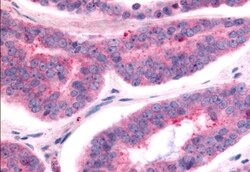

TAOK1 Polyclonal Antibody for IHC (P)

| Immunohistochemistry (Paraffin) | |